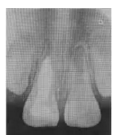

1b 術后1周X線片